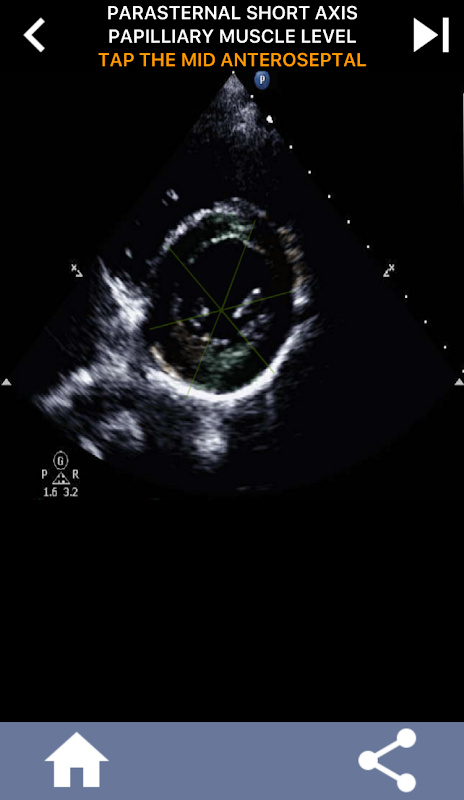

Quiz-gebaseerde visuele benadering voor het leren van de AHA-hartsegmenten: echocardiografie

Het begrijpen van de hartsegmenten van de AHA (American Heart Association) is van het grootste belang voor een cardiale sonograaf om effectief te communiceren met de cardioloog die het rapport schrijft. Door de specifieke anatomische regio's en hun overeenkomstige segmenten te kennen, kan de echoscopist eventuele afwijkingen of bevindingen nauwkeurig beschrijven en communiceren, waardoor een duidelijke en beknopte communicatie tussen beide professionals wordt gegarandeerd.

Dit begrip wordt met name cruciaal wanneer de cardioloog de precieze locatie van een probleem probeert vast te stellen of wanneer de dienstdoende arts een probleem binnen een specifieke regio identificeert, waardoor de echoscopist wordt gevraagd om het overeenkomstige segment nauwkeurig weer te geven, zoals de middelste onderwand. Het hebben van een volledig begrip van de AHA-hartsegmenten is dus een essentiële vaardigheden.

Deze app test je kennis met behulp van echte echobeelden, wat ik vaak de beste lesmethode vind.